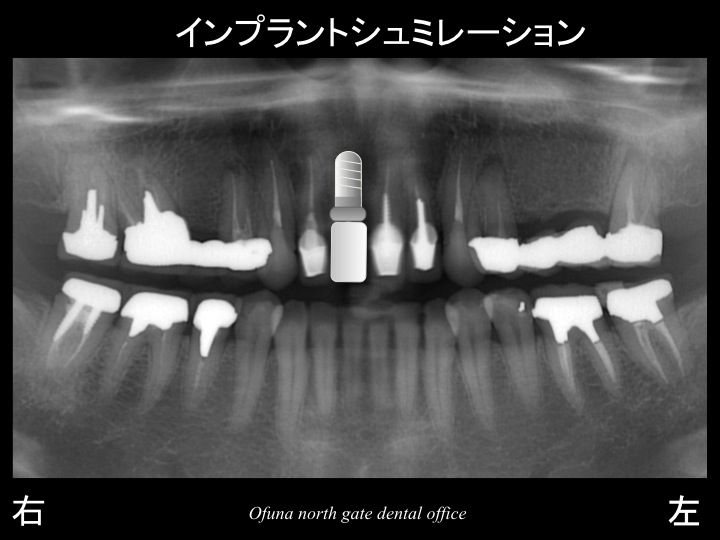

ここで この患者様の口腔内全体を見てみましょう!

以下のレントゲン写真の赤丸は神経がない歯です。

ほとんどの歯が神経がありません。

今後が本当に心配な方です。

抜歯後の治療方針として患者様はインプ

ラント治療をご希望されました。

次のレントゲンは治療終了後になります。

使用したインプラントはアンキロス インプラント です。